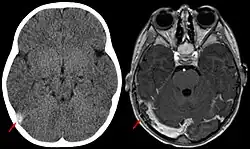

Diagnose

Door de variatie in de klinische presentatie is het soms moeilijk om de diagnose te stellen. De diagnose CVT kan worden vastgesteld met behulp van een scan van het hoofd; een CT-venografie, of MRI hersenen in combinatie met een MR-venografie. Slechts in zeldzame gevallen is een conventionele angiografie noodzakelijk. Bij de helft van de patiënten met CVT is er op de scan een veneus herseninfarct zichtbaar, wat vaak bestaat uit een combinatie van oedeem en kleinere hersenbloedingen.